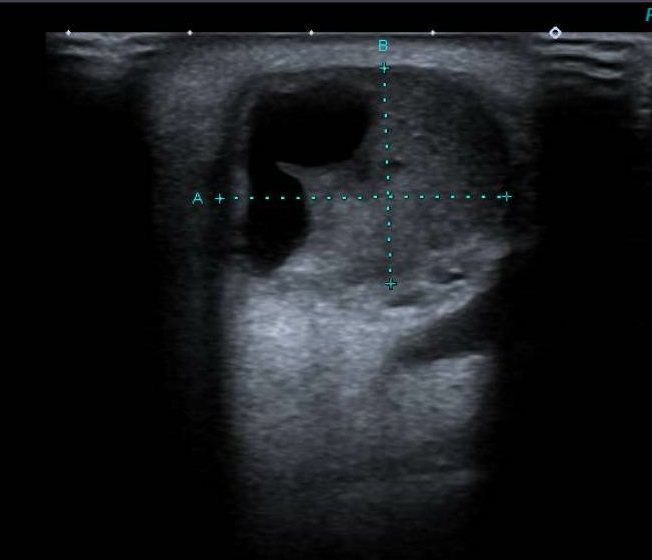

Se realiza ecografía en consulta para filiar la lesión dado el amplio diagnóstico diferencial posible.

Hallazgos ecográficos

Se objetiva nódulo quístico de 23x17 mm en parótida derecha, no vascularizado y sin adenopatías acompañantes.